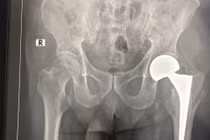

Thay khớp háng nhân tạo ở người cao tuổi luôn là một trong những thách thức đối với kíp gây mê và phẫu thuật viên. Mới đây, khoa Chấn thương chỉnh hình đã thay khớp háng nhân tạo thành công cho cụ bà 107 tuổi.

(khoahocdoisong.vn) - Bệnh viện Chợ Rẫy TPHCM đã phối hợp đa chuyên khoa tiến hành phẫu thuật thay khớp cổ xương đùi thành công cho 1 trường hợp lớn tuổi - bệnh nhân N.T.K. (106 tuổi). Đây là bệnh nhân lớn tuổi nhất được thay khớp cổ xương đùi tại Bệnh viện Chợ Rẫy TPHCM.

(khoahocdoisong.vn) - Trước đây, những bệnh nhân trên dưới 100 tuổi nếu không may bị gãy xương ở chân thông thường chịu cảnh tàn phế. Tuy nhiên, từ nhiều năm nay, Khoa Phẫu thuật khớp, Bệnh viện T.Ư Quân đội 108 đã cứu chữa thành công cho nhiều trường hợp bệnh nhân trên dưới 100 tuổi bị gãy xương đùi.

(khoahocdoisong.vn) - Người cao tuổi khi bị ngã không nên sợ phẫu thuật vì nằm thêm một ngày là bệnh thêm nặng. Việc thay khớp háng thành công sẽ giúp người cao tuổi bị té ngã có thể phục hồi sức khỏe và đi lại được.

(khoahocdoisong.vn) - Người già bị gãy cổ xương đùi (GCXĐ) chớ nên sợ phẫu thuật, nằm thêm một ngày là bệnh thêm nặng. Với công nghệ thay khớp háng bán phần và toàn phần người già, thậm trí trên 90 bị GCXĐ, vẫn có thể phục hồi sức khỏe và đi lại được.